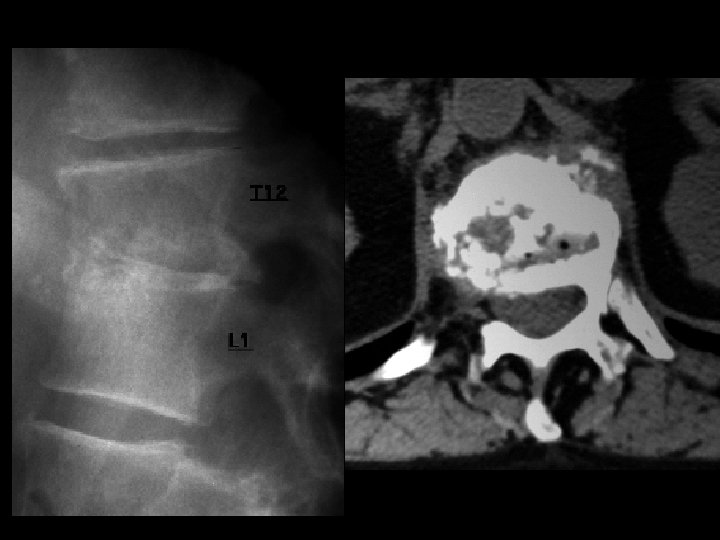

Discitis • Findings: – T 12 -L 1 disc space narrowing with endplate destruction – CT demonstrates presence of gas • ddx: – NONE! – This is an Aunt Minnie!